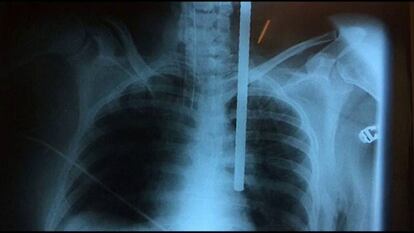

Virginia trató de salvar a su nieta de caer desde una azotea cuando ambas se precipitaron al vacío en Perú. La abuela abrazó a la pequeña para evitar el golpe y se clavó un hierro que entró por la clavícula llegando hasta el pulmón. En el hospital los médicos observaron que la barra de metal entraba en el cuerpo a varios milímetros de la arteria aorta; tenían que operar a la paciente a vida o muerte. Gracias a la pericia médica de los profesionales, Virginia puede contar la experiencia un mes después de lo ocurrido. Por el acto heroico de esta abuela la pequeña no sufrió heridas graves.